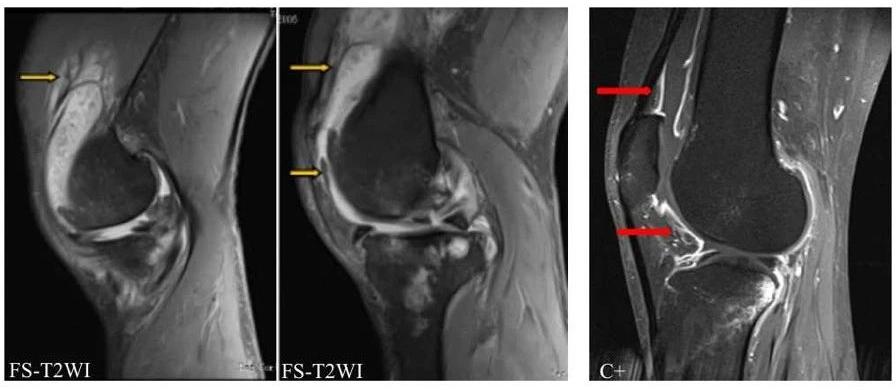

影像表现:髌上囊及关节腔积液;滑膜弥漫性增厚;髌上囊可见多发绒毛状、树枝状脂肪信号影,T1WI呈高信号,脂肪抑制序列呈低信号,与皮下脂肪信号一致。其他略。

诊断:膝关节滑膜树枝状脂肪瘤

3、MR表现常具有特征性,表现为滑膜弥漫性增厚,可见树枝状、绒毛状、结节状或棕榈叶状的异常信号,T1WI呈高信号,T2WI呈稍高信号,脂肪抑制序列呈低信号,各序列与皮下脂肪信号类似,梯度回波序列为高低混杂信号。常伴有大量关节积液,因此在T1WI序列上高信号的肿瘤组织与低信号的积液形成十分鲜明的对比。增强扫描增厚的滑膜明显强化,但脂肪成分无强化。多合并有关节腔及髌上滑膜囊不同程度积液,部分可以合并软骨损伤及软骨下骨髓水肿、囊变等。

上图,色绒患者,可见T1WI、T2WI压脂双低信号。